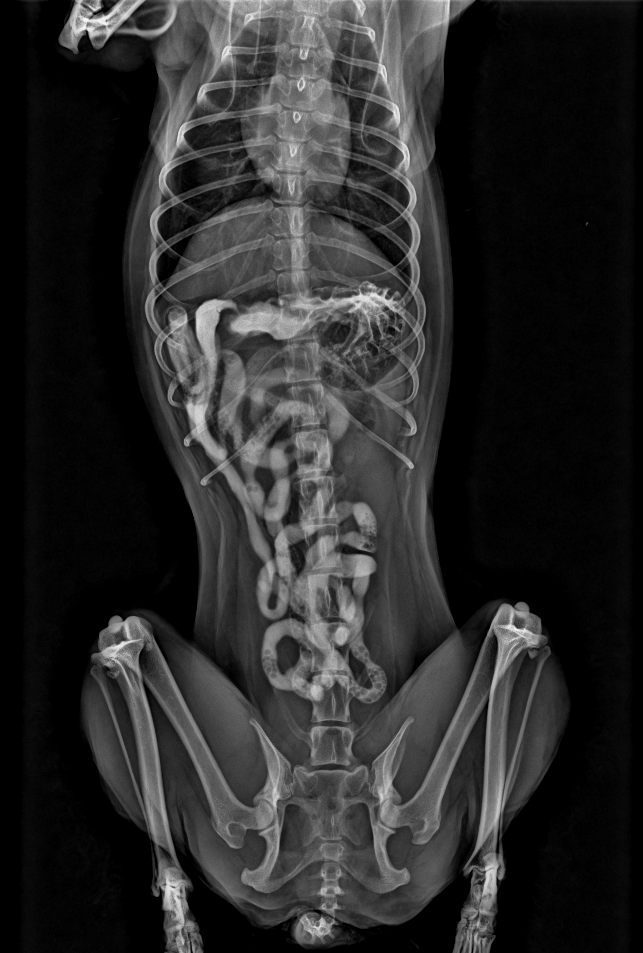

Share some clinical x-ray images by our veterinary DR system YSX056-PL with flat panel detector YSFPD-V1717X VET.

Here we'd like to share some clinical x-ray images by our veterinary DR system YSX056-PL with flat panel detector YSFPD-V1717X VET.